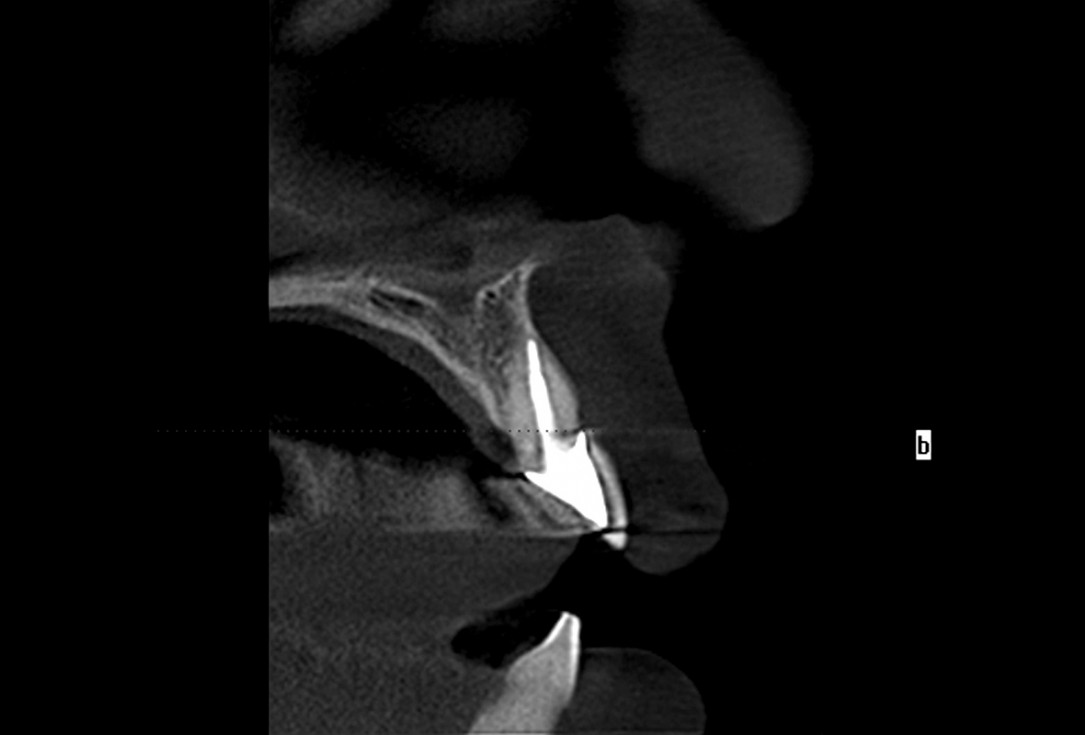

Pre-operative situation showing tooth 21 with deep periodontal pocket. Tooth presented with mobility grade III.